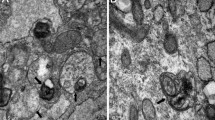

Autophagosome measurement

Supraspinati were cut into 1-mm3 tissue blocks at 4 °C and fixed with stationary liquid for 24 h at 4 °C. Then, tissue samples were fixed for another 2 h in 1% osmic acid. After uranyl acetate (Merck, 10011) staining for 3 h under room temperature and dark conditions, samples were washed with redistilled water and dehydrated using graded ethanol. Dehydrated tissues were placed at a mixture of ethanol and epoxypropane (Aladdin, P109309) (1:2) for 10 min, epoxypropane twice for 10 min, mixture of epoxypropane and embedding medium (1:1) for 40 min, mixture of epoxypropane and embedding medium (1:4) for 3 h and then tissues were embedded using embedding medium at 4 °C overnight and subsequently polymerized at 60 °C for 48 h. After making histological sections, the tissue sections were stained with uranyl acetate and lead citrate and autophagosome was observed under a transmission electron microscope and photographed.

Administration with leucine inhibits autophagy levels in atrophying muscles

A previous study has confirmed that autophagy in skeletal muscle presents sustained generation of autophagosomes that can maintain for days (Mizushima et al. 2004). Thus, we performed transmission electron microscopy analysis to assess the production of autophagosomes in these models and found that there was no damage on histological structure and no autophagosome vesicles in the sham control group. But cutting off the muscle obviously destroyed muscular tissue structure and promoted the numbers of autophagosomes and autophagolysosomes. Once treated with leucine, the destroyed muscular tissue was restored to normal level and the production of autophagosomes and autophagolysosomes was inhibited (Fig. 3a, b). Next, we performed immunoblotting to further verify the autophagy inhibition effect of leucine on atrophying muscles. We discovered that tendon transection induced the increase of Atrogin-1 and MuRF1 expressions that were repressed in the condition of leucine-containing diet treatment (Fig. 3c), which suggested that leucine supplement weakened the level of Atrogin-1/MuRF1 and subsequently improved the process of supraspinatus atrophy. We also evaluated the expression of key regulators for autophagy in muscle and detected that transcription factor FoxO3 and its downstream signals LC3 and Bnip3 that were important for the process of autophagy in muscle were upregulated in the tendon transection group but leucine treatment made them recover to the normal level (Fig. 3c). Quantitative analysis of these protein expressions also showed that leucine supplementation significantly blunted tendon transection-evoked muscle atrophy and the formation of autophagosomes (Fig. 3d).

(a–a”) Transmission electron microscopy scanning of the autophagosomes vesicles in atrophying supraspinatus. Red arrow indicates autophagosomes and white arrow indicates autophagolysosomes. (b) Quantitative analysis of the number of vesicles in TEM scanning assay. (c) Expression of LC3, Atrogin-1, MuRF1, Bnip3, and FoxO3 was evaluated by immunoblotting in different supraspinatus tissues. GAPDH was served as the internal control. A: sham + normal diet; B: muscle cutoff + normal diet; C: muscle cutoff + leu diet. (d–d””) Relative quantitative analysis of LC3, Atrogin-1, MuRF1, Bnip3, and FoxO3. *p < 0.05; **p < 0.01

Numerous evidences have verified that AKT is the potent autophagy inhibitor in skeletal muscle and that the PI3K/AKT/mTOR pathway is the crucial element in muscle atrophy but whether leucine-mediated anti-atrophic effects were correlated with PI3K/AKT/mTOR signaling transduction remains unclear. As shown in Fig. 4(a–a””), tendon transection-mediated supraspinatus muscle atrophy was crippled by leucine administration. However, through MRI scanning, we observed that injection with LY294002 (PI3K inhibitor) and Rapamycin (mTOR inhibitor) distinctly blocked the anti-atrophic effects of leucine (Fig. 4a–a””). The promotion effect of leucine on supraspinatus muscle was also blunted in the presence of LY294002 and Rapamycin through measuring muscle wet weight (Fig. 4b). Besides, the protective role of leucine on pathological changes of atrophying muscle was significantly repressed in the treatment with PI3K and mTOR inhibitors (Fig. 5a–b””). As shown in Fig. 5a–a, we found that the area of inflammation infiltration, fat accumulation, muscle fibrosis and fiber cross-sectional area was obviously enhanced in the inhibitor group compared to the leucine alone-treated group (Fig. 5a–c). PI3K and mTOR inhibitors also blunted leucine mediated by the decreased characterization of autophagy in the RCT group accompanied by a bigger amount of autophagosomes and autophagolysosomes in comparison with the leucine-treated group but slightly less than the RCT group fed with standard chow diet (Fig. 5d–e). Our findings indicate that the PI3K/AKT/mTOR pathway participated in the process of leucine-mediated improvement of muscle atrophy and autophagosome formation.

(a–b””) HE staining of supraspinatus sections in sham control and RCT group treated with normal, leucine, leucine + LY294002, and leucine + Rapamycin, respectively. (c) Quantitative analysis of fiber cross sectional area. (d–d””) Transmission electron microscopy scanning of the autophagosomes vesicles in supraspinatus in the five groups. Red arrow indicates autophagosomes, and white arrow indicates autophagolysosomes. (e) Quantitative analysis of the number of vesicles in TEM scanning assay. *p < 0.05; **p < 0.01